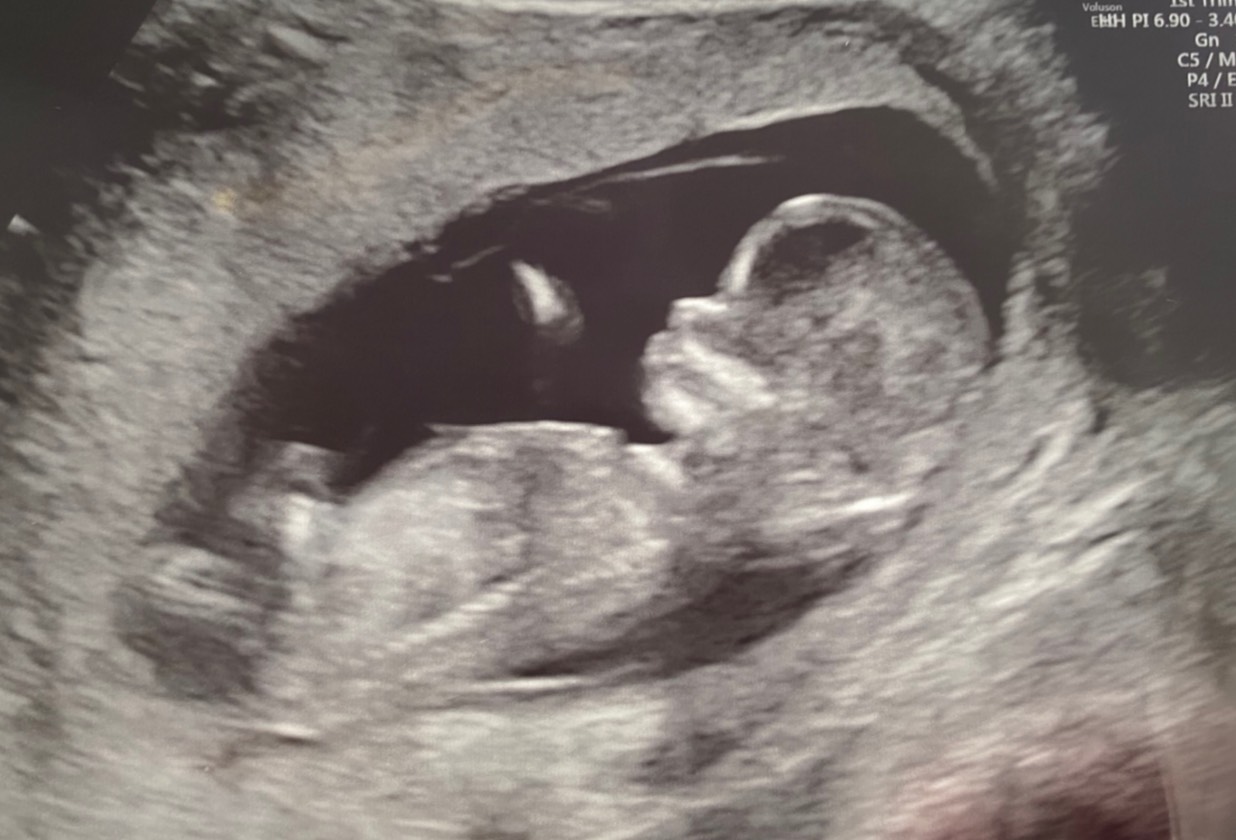

妊娠12w2dの赤ちゃん

今から親ばかを発揮致します。

なんて可愛い横顔なのでしょうか!!

これはもうぺっぴんさんに違いない!!!

以上です(笑)